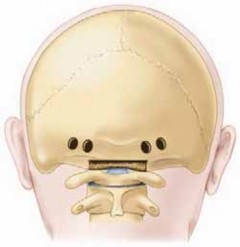

1. At the level below the transverse sinus, four transverse-oriented holes are drilled through both cortices of the occiput with a high-speed diamond drill.7

1. The holes are aligned transversely with two on each side of the midline. At least 1 cm of intact bone should be left between the holes to prevent wire pull-out through the skull (

TECH FIG 1A

).

2. Surgical loupes and a headlamp are recommended for this procedure.

2. Using a high-speed diamond burr, the surgeon makes a transverse-oriented trough into the base of the occiput to fit the rectangular superior part of the iliac autograft.

3. A single corticocancellous autograft (3 × 4 cm) is harvested through an oblique incision over the posterior superior iliac spine.

4. A rectangular graft is taken. The surgeon creates a notch in the inferior base of the graft to be suitable for the base of the spinous process of the second or third vertebra (

TECH FIG 1B

5. 16- or 18-gauge wire is passed through the burr holes on each side of the midline and the wire is looped on itself (

TECH FIG 1C,D

48. A sublaminar wire is placed under the ring of C2 or C3 (or passed through the base of the spinous process, if structurally sufficient, or if there is canal stenosis).

1. The left side of the graft accepts the left end of the wire and the right end of the graft accepts the right end of the wire (

TECH FIG 1E

49. The edges of the graft are contoured to fit appropriately into the occipital trough and around the base of the spinous process (

TECH FIG 1F

50. The wires are tightened over the graft in figure 8 shape. After satisfactory tightening the edges of the wire are cut and bent away from skin (

TECH FIG 1G,H

Transverse sinus TECH FIG 1 • A. Four transverse-oriented occipital burr holes and rectangular trough. B. Corticocancellous rectangular graft with a notch at the inferior base ofA B the graft. _(continued)_EH